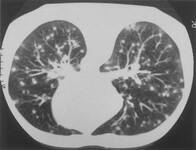

Lung CT scan showing classic 'snowstorm' appearance of acute histoplasmosis

Public Health Image Library, US Centers for Disease Control and Prevention